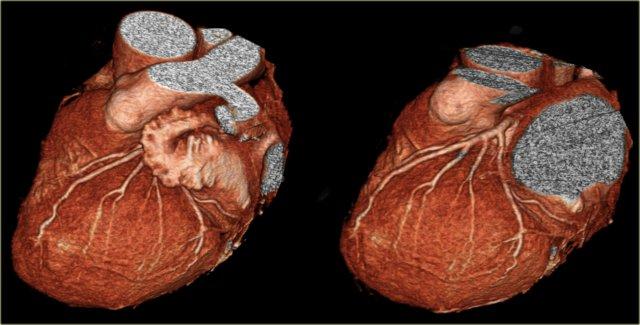

Bên trái là hình ảnh CT cắt ngang.

LCA đi giữa đường ra thất phải ở phía trước và nhĩ trái ở phía sau, rồi phân chia thành LAD và Cx.

Trên hình bên trái, chúng ta thấy thân chung động mạch vành trái phân chia thành

- Cx với nhánh bờ tù (OM)

- LAD với các nhánh chéo (DB)

Trên các hình ảnh dựng hình thể tích (volume rendered), cần loại bỏ tiểu nhĩ trái để quan sát rõ LCA.